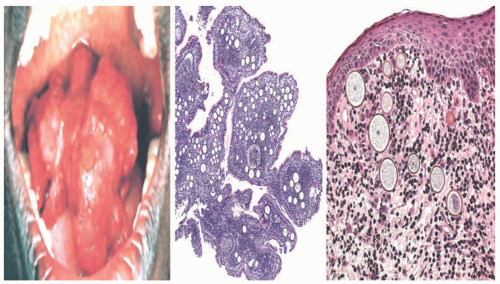

Symptoms of upper respiratory tract infection predate the development of soft polyps with a strawberry-like appearance, typically on the mucosal surfaces of the nose or eyes. The polyps are usually vascular and friable, and they bleed easily.

Histologic Findings

The skin lesions begin as papillomas that become more verrucoid with time and are associated with mucoid surface material. The surface epithelium and submucosa contain numerous globoid cysts that range from 10 to 200 microns in diameter (Figure 20-9). Some may be partially collapsed, assuming a semilunar shape. Spores are released from mature sporangia by rupture of their walls. They develop into small trophic cysts that contain a basophilic karyosome and distinct chitinous walls. H&E-stained sections clearly demonstrate the organisms, and they are stained by the PAS and GMS methods. The inner portion of the walls of larger sporangia may be birefringent.